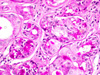

CASO N° 2 (Dr. Elismauro e Dr. Delgado)

Paciente do gênero masculino, 85 anos de idade, apresenta um aumento de volume na maxila esquerda.